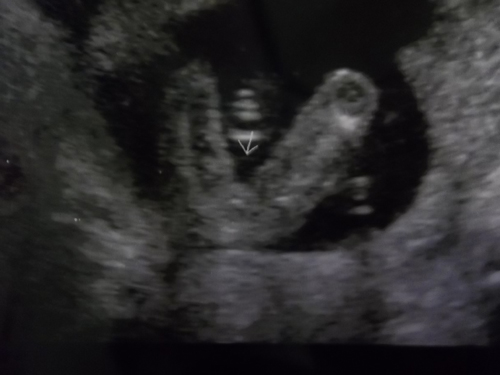

AND....potty shot at 20w (actually 19+5)

Attachment 2767